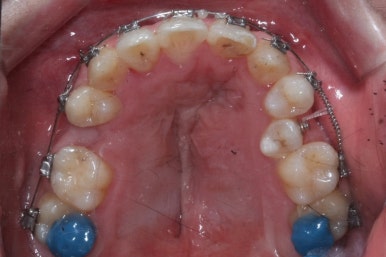

좁아져 있는 위턱뼈를 가로로 넓혀주기 위해서 악궁확장장치를 사용했습니다.

악궁확장이 시작될 시점과 악궁확장을 다 진행했을 시점의 비교입니다.

확실히 좁아져 있던 가로 넓이가 넓어진 것을 볼 수 있습니다.

악궁확장장치는 바로 제거할 경우 다시 원상태로 폭이 좁아질 수 있으므로 3~6개월은 유지해야 합니다.